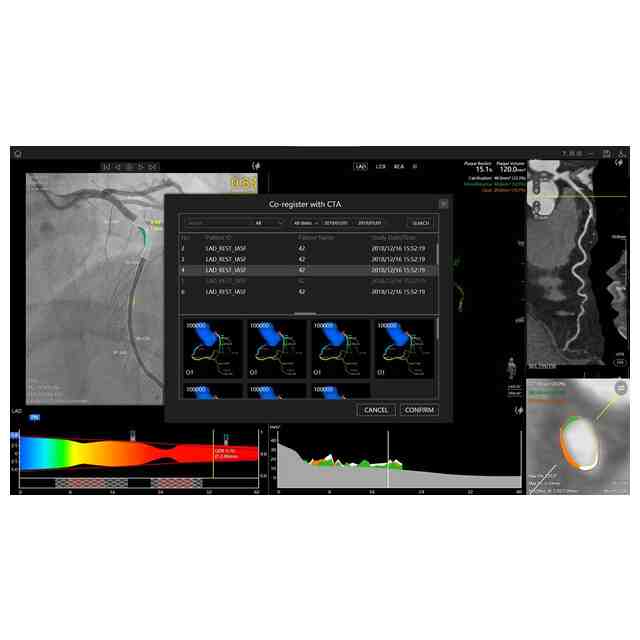

画像図及び変化後を示す画像図1~3は、例えば、複数の医療用画像を登録した後に表示して分析するために用いられる。使用状態を示す参考図1~6、変化後を示す画像図1の使用状態を示す参考図1~5、変化後を示す画像図2の使用状態を示す参考図、及び、変化後を示す画像図3の使用状態を示す参考図は、医療用画像データを分析するに際し、表示される図を示したものである。変化後を示す画像図1は、画像図における下方において黄色で示されたウインドウの右上隅にある「非表示」ボタンが押されると表示される画像である。変化後を示す画像図2は、変化後を示す画像図1における黄色で示された左端のウインドウがダブルクリックされると表示される画像であり、変化後を示す画像図2における黄色で示されたウインドウがダブルクリックされると画像図に戻る。変化後を示す画像図3は、画像図における黄色で示された中央のウインドウがダブルクリックされると表示される画像である。

図面中、黄色で示された部分以外の部分が部分意匠として意匠登録を受けようとする部分である。